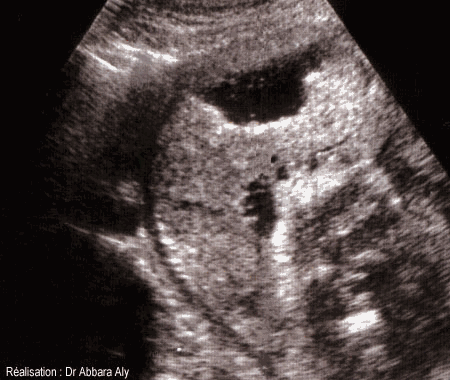

Coupe longitudinale du placenta et de l'utérus montrant l'hématome rétroplacentaire

(ou le décollement prématuré du placenta non bas inséré) à 33 semaines d'aménorrhée